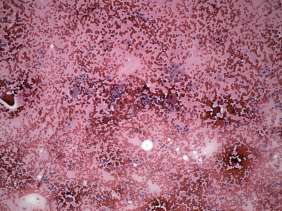

A right lobectomy was performed. Histopathology disclosed benign hyperplastic nodules and chronic lymphocytic thyroiditis.